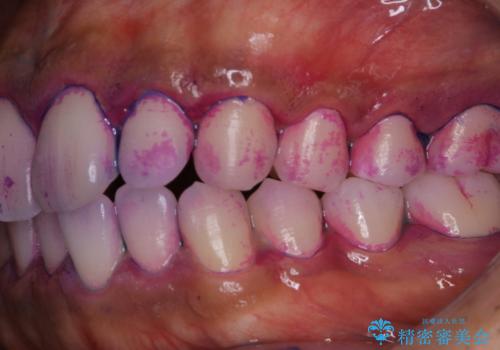

- 特に症状など気になるところはないが、メンテナンスして欲しいとのことでした。染め出しをしてのブラッシング指導とPMTC30分コースを行いました。

染め出しをすると、現在付着しているプラークを確認できて、今後の正しいハミガキの方法を知るチャンスとなります。